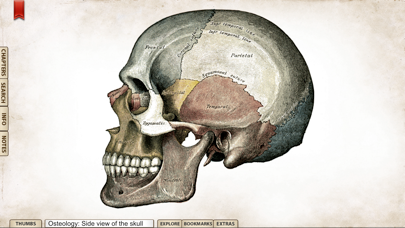

1. 'Gray's Anatomy', the renowned classic anatomical book by Henry Gray was first published in 1858 and is considered by many to be one of the most iconic and significant medical books of all time.

2. Gray's Anatomy is now available on the iPhone and iPod Touch using the highest resolution images possible.